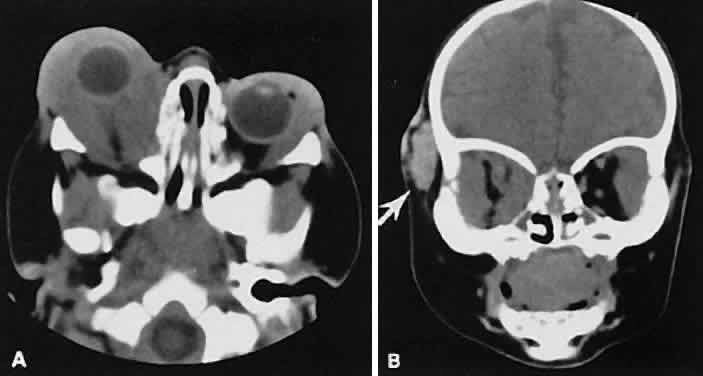

The edema and inflammatory infiltrate that accompany infections are indistinguishable from that associated with orbital inflammations. The presence of sinus disease, however, is a more constant feature with infections, because the sinus represents the infectious nidus in most cases (Fig. 9). In addition to the frequent appearance of sinus disease, the adjacent EOM is invariably enlarged. Less often, orbital infections may be transmitted through the blood, related to a retained foreign body, or spread from the lids. Chandler and colleagues47 classified orbital infections into five groups. Group 1 (preseptal cellulitis) represents inflammatory edema and reflects congestion of venous outflow. Group 2 has actual orbital infiltration/edema with mass effects and functional deficits. Group 3 includes patients with subperiosteal abscesses. Most of these dome-shaped subperiosteal abscesses are located along the medial wall. Group 4 includes patients with orbital abscesses who may display a ring-enhancing lesion with mass effect. Group 5 represents intracranial extension of the inflammation into the cavernous sinus or sinuses, which appear engorged and opacified.

Fig. 9. Orbital cellulitis. A. Axial view shows a subperiosteal soft-tissue mass displacing the medial rectus muscle. The ethmoidal sinus is opacified secondary to inflammatory disease, which invariably precedes the orbital inflammation. B. Coronal view further shows the subperiosteal and ethmoidal sinus inflammation. Inflammation changes also are seen in each maxillary sinus.